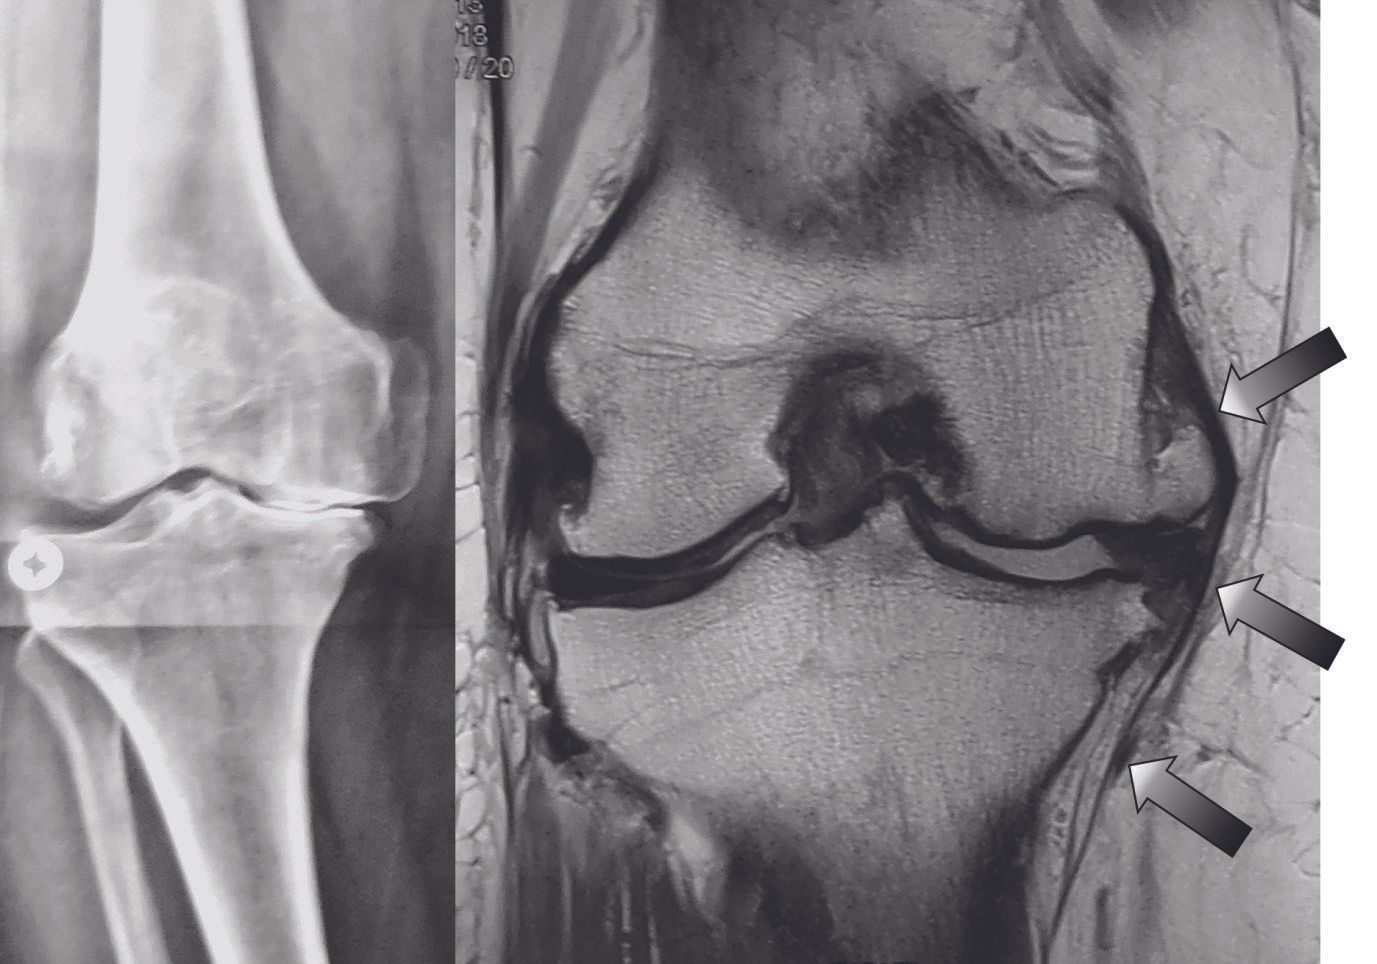

1. The superficial MCL does not contract in varus deformities

- Osteophyte presence, location and size

- Reduction osteotomy3 of the posteromedial tibial flare helps to achieve correction by reducing the tenting of the MCL